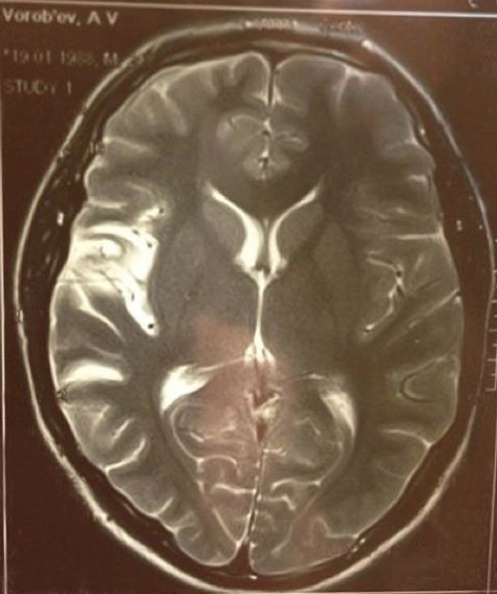

«От „точки невозврата“ прошло 3 года и несколько дней. Жизнь удивительная штука, я вам скажу. Мой поражённый на 25% мозг работает ещё быстрее, чем когда-либо. Я бегаю, прыгаю, пою и танцую, пишу музыку, снимаюсь в кино и снимаю его сам. И иногда на концертах пою мимо нот, так как больше не слышу этого, потому что восстановиться на 100% уже невозможно. Иногда не могу подняться по лестнице, потому что сердце так колотится, что чуть не разбивает грудную клетку изнутри, приходится сидеть на ступеньках, смотреть на подрагивающие руки и, смеясь над собой, мечтать о законопроекте, который вообще отменит лестницы:) Пью таблетки для разжижения крови, и живу полной жизнью, — каждый день, не ограничивая себя ни в чем. Организм перестал нуждаться в отдыхе, и вообще перестал требовать время на сон без снотворного, и это дарит много времени, которое не хочется терять. Мне повезло быть молодым, когда случился инсульт, и ещё больше повезло остаться жить. Я научился ценить жизнь и время, которое нам всем отведено на земле. Жизнь действительно удивительная штука, и она, действительно, похожа на коробку конфет, — иногда эти конфеты горькие, и дарят только боль, иногда — сладкие, как поцелуй любимой женщины… Но эта коробка никогда не пуста. Я совершенно точно понял одно- если и есть Бог, то он очень любит меня:)» — откровенно написал артист.